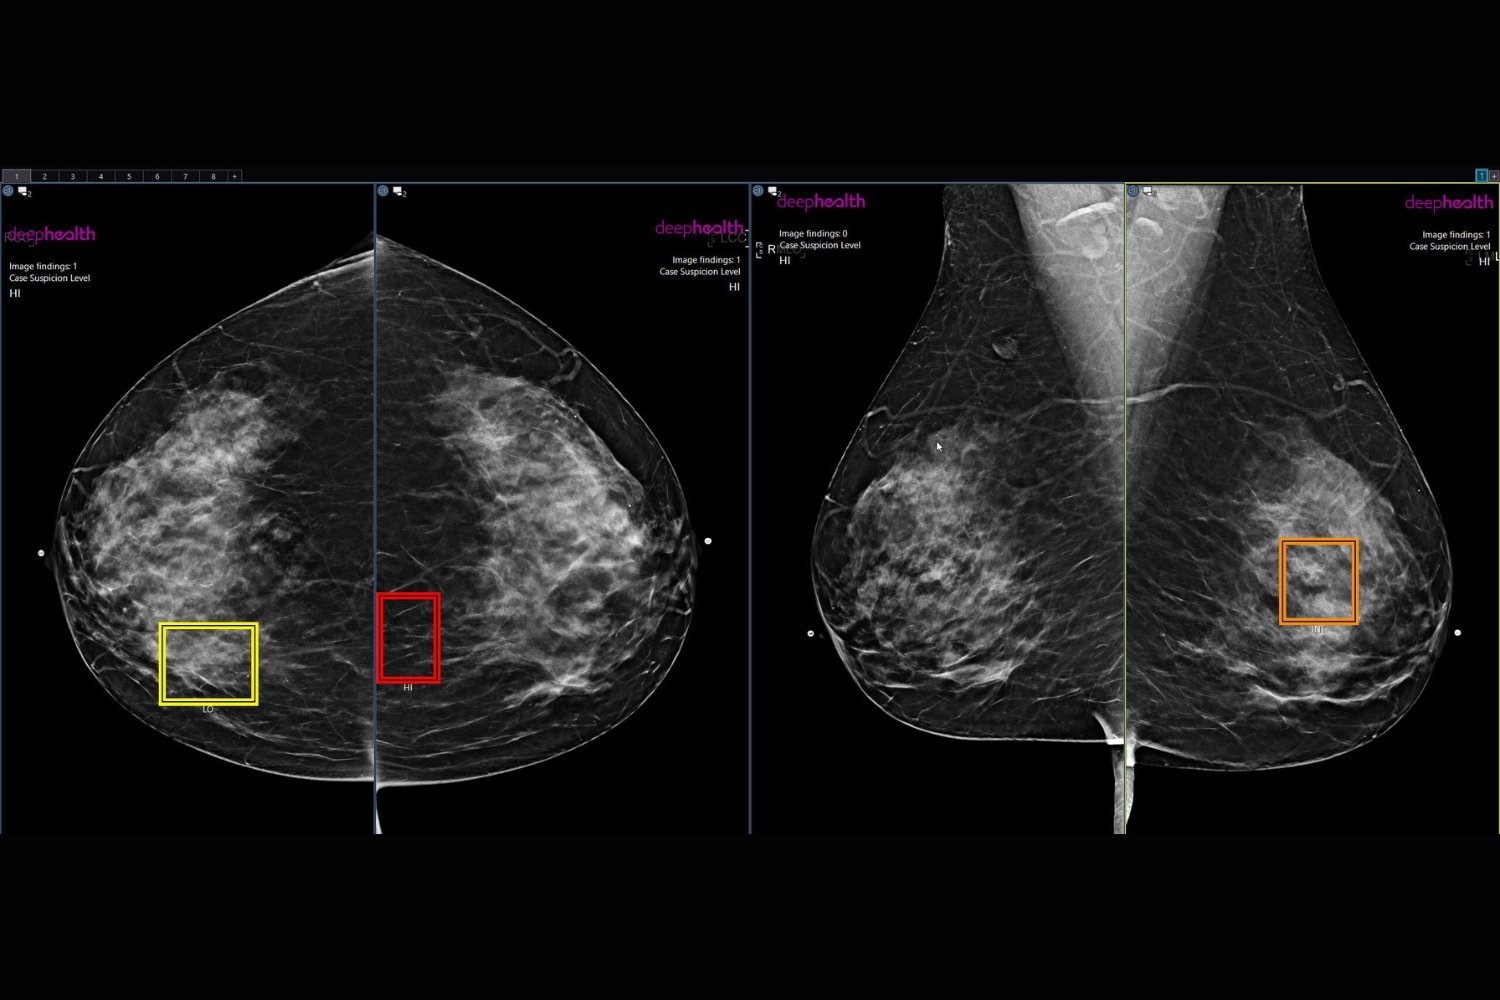

Para peneliti pada pertemuan tahunan Masyarakat Radiologi Amerika Utara (RSNA) tahun ini mengungkapkan bahwa kanker 21% lebih mungkin terdeteksi pada wanita yang membayar ekstra untuk program skrining kanker payudara yang ditingkatkan dengan AI. Temuan mereka, yang dipresentasikan pada pertemuan tahunan dan dirinci dalam pernyataan RSNA, menegaskan potensi AI untuk menjadi “mata kedua” bagi ahli radiologi.

“Ini adalah laporan pertama mengenai hasil dari sebuah program yang memberikan tinjauan yang ditingkatkan dengan dukungan AI sehingga pasien dapat memilih untuk ikut serta,” kata Bryan Haslam, chief product officer di DeepHealth yang memimpin penelitian tersebut, dalam pernyataannya.

Studi ini mempertimbangkan 10 praktik klinis yang menawarkan program skrining mamografi bertenaga AI yang dibayar sendiri dan sesuai dengan FDA kepada pasien. Hasil rontgen wanita yang mengikuti program ini ditinjau oleh ahli radiologi payudara dan kemudian oleh perangkat lunak AI. Jika tinjauan tersebut tidak konsisten satu sama lain, ahli radiologi kedua akan memberikan tinjauan ketiga.

“Program peninjauan yang ditingkatkan yang digerakkan oleh AI memanfaatkan AI dalam alur kerja baru untuk memastikan wanita dengan temuan mencurigakan mendapatkan perawatan tingkat ahli yang dapat membantu mendeteksi lebih banyak kanker payudara secara dini,” tambah Haslam. “Jumlah perempuan yang memilih program ini kini mencapai 36% dan terus bertambah, dan tingkat deteksi kanker terus jauh lebih tinggi pada perempuan tersebut.”

Faktanya, dari 747.604 wanita yang menjalani mammogram selama setahun, tingkat deteksi kanker sekitar 43% lebih tinggi pada mereka yang mengikuti program dibandingkan dengan mereka yang tidak. Para peneliti mencatat tingkat yang lebih tinggi pada 10 praktik dalam penelitian tersebut. Meskipun mereka mengaitkan 22% peningkatan tersebut dengan fakta bahwa perempuan dengan risiko lebih tinggi terkena kanker lebih besar kemungkinannya untuk mengikuti program ini, namun 21% peningkatan deteksi lainnya berasal dari AI.

Oleh karena itu, perempuan yang terdaftar dipanggil kembali untuk pemeriksaan tambahan dengan tingkat 21% lebih tinggi dibandingkan perempuan yang tidak terdaftar, dan nilai prediksi positif mereka terhadap kanker (kemungkinan mendapatkan hasil positif untuk kanker Sungguh menunjukkan kanker) juga 15% lebih tinggi, “menunjukkan bahwa setiap penarikan kembali menghasilkan lebih banyak diagnosis kanker pada populasi yang terdaftar,” tulis para peneliti. Dengan kata lain, penarikan kembali yang dipicu dengan bantuan AI lebih akurat.

“Data ini menunjukkan bahwa banyak perempuan yang ingin memanfaatkan AI untuk meningkatkan skrining mammogram mereka, dan ketika AI digabungkan dengan tinjauan perlindungan, lebih banyak kanker yang ditemukan,” kata Gregory Sorensen, juga dari DeepHealth dan penulis senior studi tersebut. Selanjutnya, para ilmuwan berharap untuk melanjutkan penelitian mereka dan menghilangkan bias yang diakibatkan oleh seleksi mandiri melalui uji coba terkontrol secara acak.